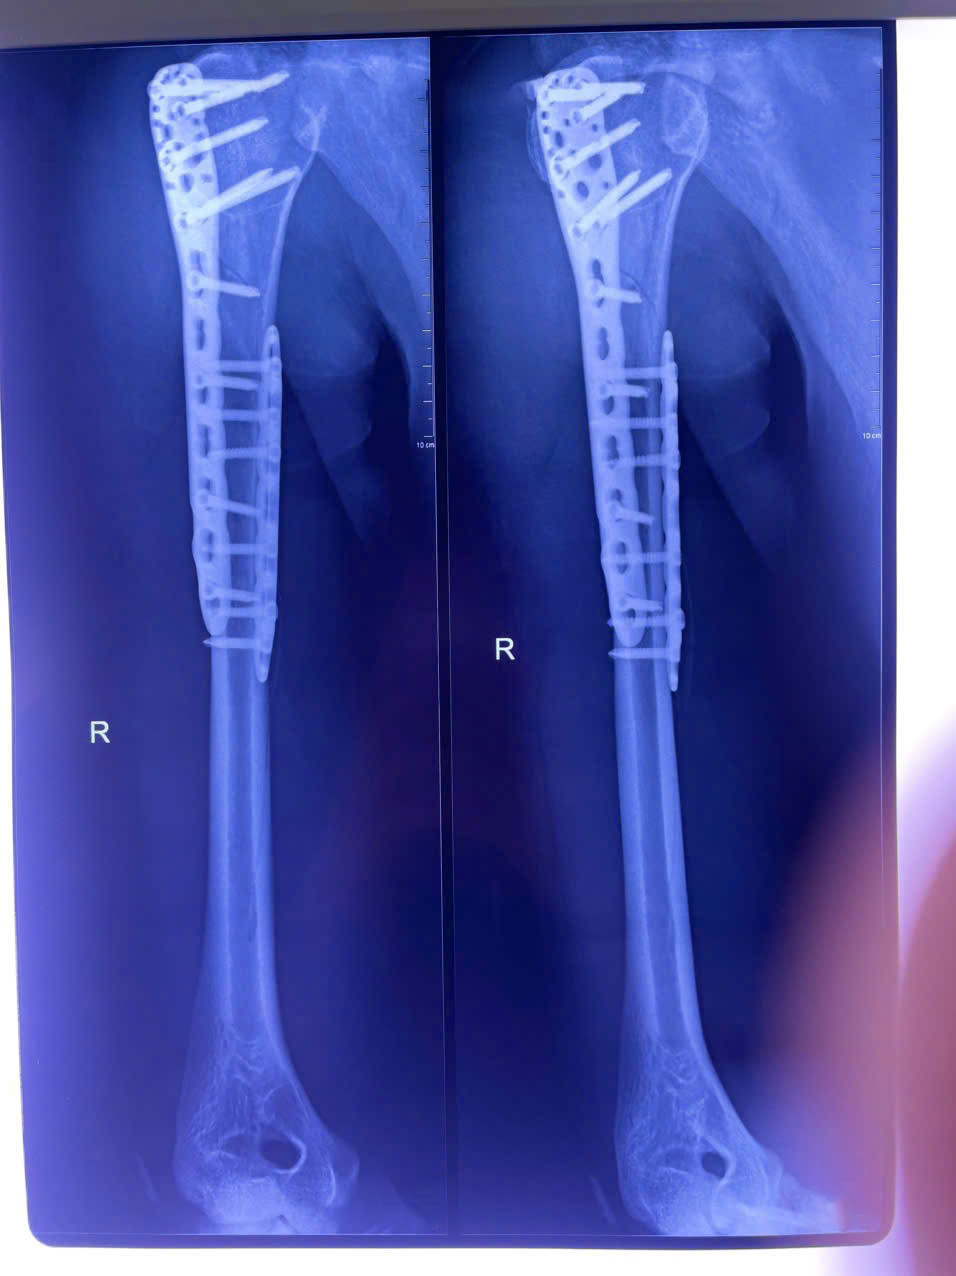

Suốt gần 3 giờ căng thẳng, ê-kíp khoa Chấn thương chỉnh hình đã thực hiện thành công ca phẫu thuật. Ổ gãy được xử lý triệt để: Rửa sạch, loại bỏ máu tụ, nắn chỉnh và cố định bằng nẹp titan cùng vít khóa. Dưới sự hỗ trợ của hệ thống C-arm hiện đại, cấu trúc xương tại vị trí tổn thương được cố định vững chắc và các đầu vít không ảnh hưởng đến mặt khớp.

Sau phẫu thuật, vị trí gãy xương cánh tay được cố định vững chắc.